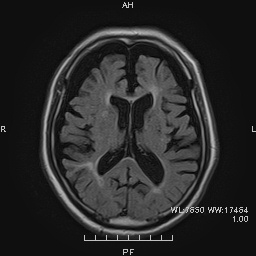

前頭側頭型認知症のMRI画像